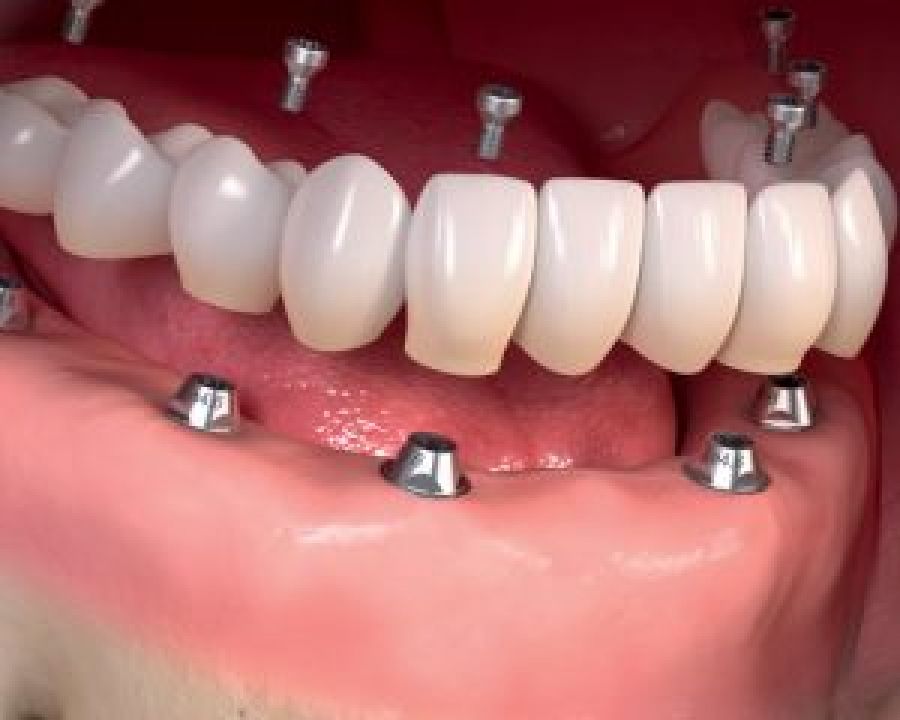

Diş implantları ağızda eksik olan dişlerin yerine konması amacıyla, genellikle titanyum veya titanyum bileşiklerinden hazırlanan yapay diş kökleridir.

Titanyum vücut dokuları ile etkileşime girmediği ve kuvvetlere karşı dirençli bir materyal olduğu için implant malzemesi olarak tercih edilir. İmplantlar daha önceden kaybedilmiş dişlerin oluşturduğu boşluklara ya da ciddi bir enfeksiyon yoksa hemen çekim sonrası diş yuvasına yerleştirilebilir.

İmplant uygulamasının asıl amacı, üzerine kullanılabilir dişler yapmaktır.

İmplantlar, sabit ya da hareketli protezler yapmak amacı ile kemiğin yeterli ve uygun olduğu durumlarda basit bir operasyonla çene kemiğine yerleştirilirler. Eğer kemik miktarı ve yoğunluğu istenilen seviyede değilse implant uygulamasından önce kemik oluşturmaya yönelik işlemler yapılması gerekebilir.